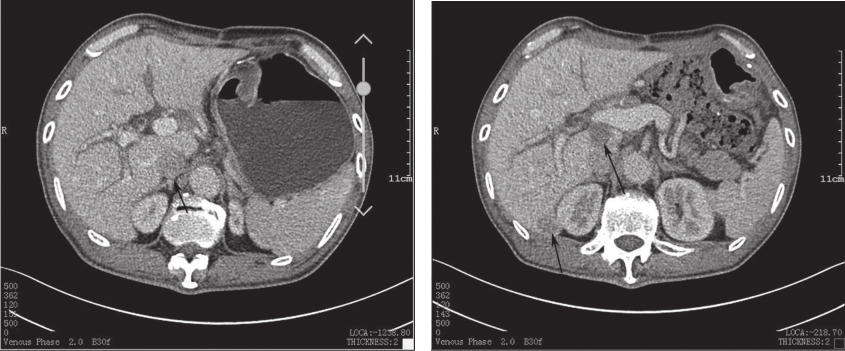

除基线CT外,患者至2018年10月共进行了3次全腹部增强CT扫描,分别在术后6个月、术后12个月和术后18个月。患者术后第18个月CT(图2)扫描复查发现“肝脏Ⅵ段和尾状叶新发结节,直径为1.9cm和2.5cm,考虑转移,余腹腔情况大致同前”,考虑十二指肠GIST术后辅助治疗期间复发,无复发生存时间为18个月。经过权衡,患者后续治疗选择伊马替尼加量至600mg/d,效果在评估中。

图2患者术后12个月和18个月的CT对比图